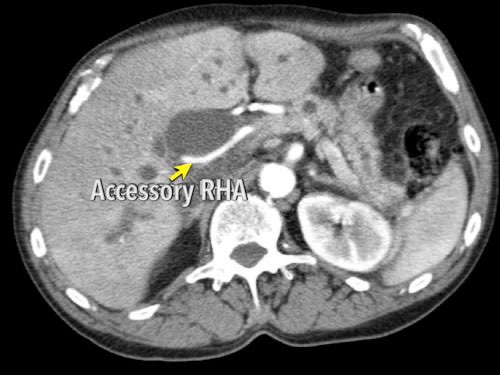

Các động mạch gan có nguyên ủy bất thường có thể là dạng phụ thêm (accessory) hoặc dạng thay thế (replaced).

Động mạch gan phải phụ thêm là một động mạch gan phải bổ sung, trong khi động mạch gan phải thay thế có nguyên ủy bất thường và thay thế hoàn toàn cho động mạch gan phải chính thức (hình minh họa).

Ở những bệnh nhân dự kiến phẫu thuật tụy, điều quan trọng là cần đặc biệt chú ý tìm kiếm nguyên ủy bất thường của động mạch gan phải hoặc động mạch gan chung.

Các động mạch này xuất phát từ phía phải của động mạch mạc treo tràng trên (SMA) và đi qua vùng lân cận đầu tụy, làm tăng nguy cơ xâm lấn của khối u hoặc tổn thương do phẫu thuật.

Tần suất được ghi nhận của các bất thường đặc hiệu này lần lượt là 11-21% và 0,5-5%.

Hình CT axial cho thấy một động mạch gan phải phụ thêm (mũi tên vàng) đi qua vùng lân cận một khối giảm tỷ trọng ở đầu tụy (đầu mũi tên).